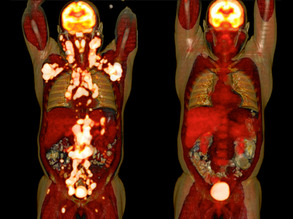

Circulating Ideas